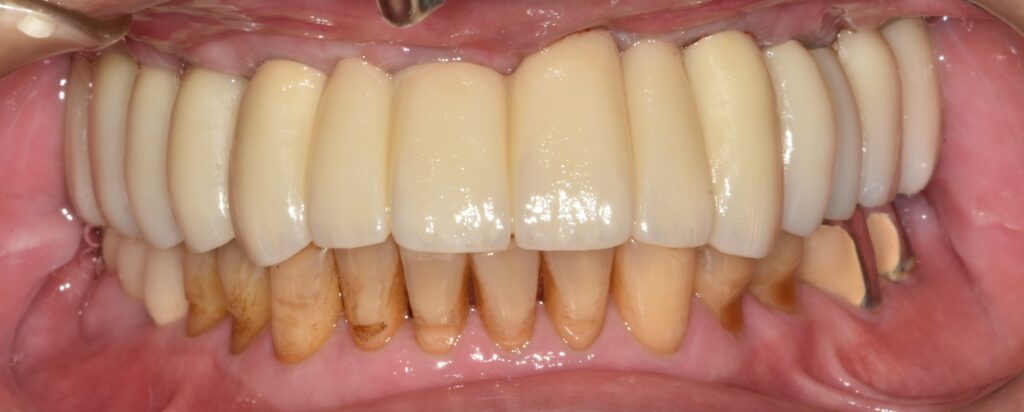

최종 보철 장착

충분한 적응 기간을 거친 후, 문제가 없음을 확인하고 최종 보철을 제작 및 장착하였습니다.

이 단계에서는 단순히 치아를 넣는 것이 아니라 기능과 안정성까지 고려한 정밀한 마무리 과정이 이루어집니다.